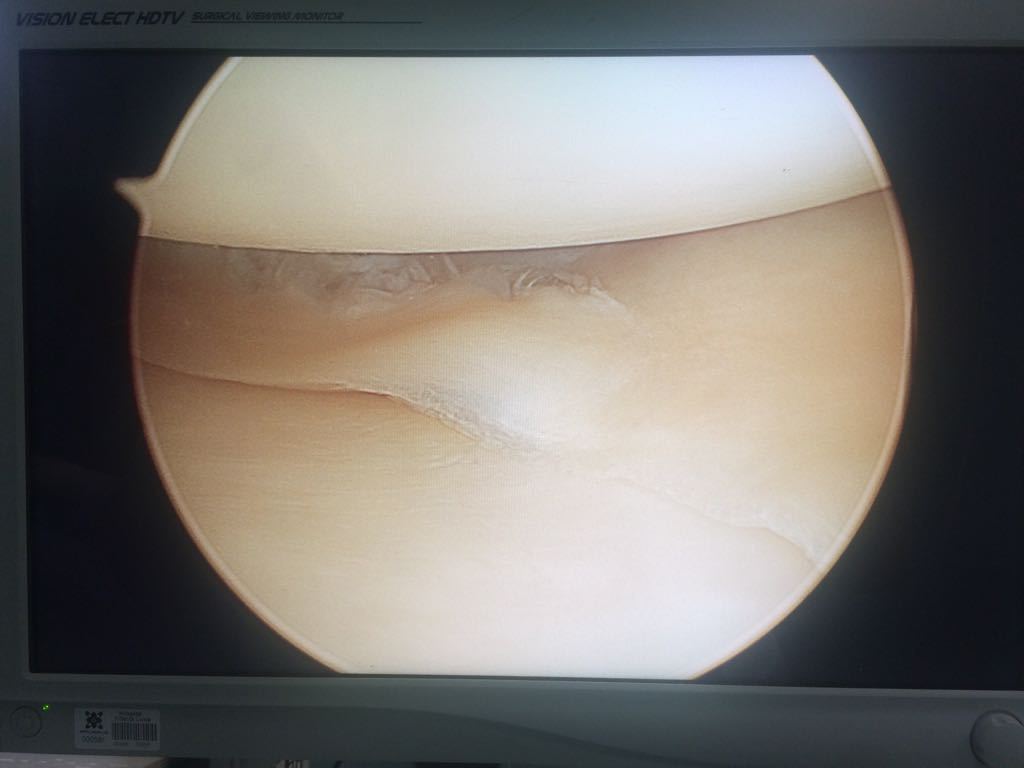

Lesión de menisco. El menisco está formado por un cartílago fuerte y gomoso, y actúa como amortiguador de choque entre la tibia y el fémur. Si giras la rodilla en forma repentina mientras cargas peso sobre ella, puedes romperte el menisco

Cirugía artroscópica. Dependiendo de la lesión, es posible que se pueda examinar y reparar el daño de la articulación con una cámara de fibra óptica y herramientas largas y delgadas que se insertan a través de unas pequeñas incisiones alrededor de la rodilla.